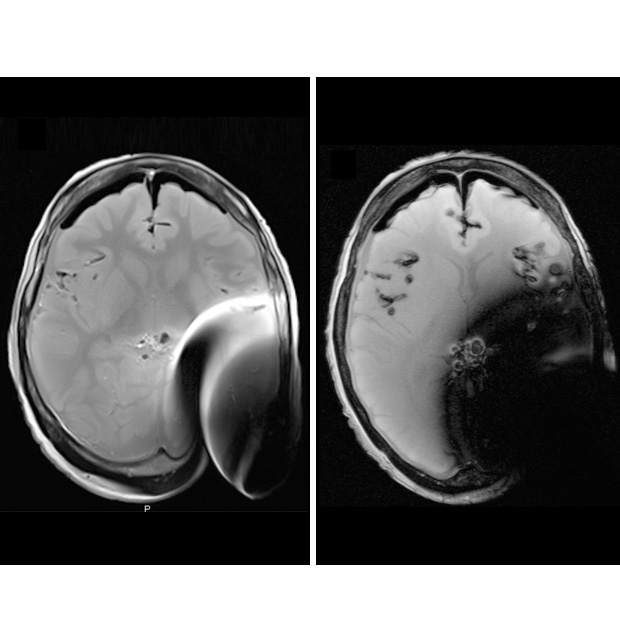

In fact, when asked radiologists stated that they could not make an accurate diagnosis from images scanned with 3 Tesla with the magnets in place because of the interference created by the magnets7 (see table below). This can be clearly seen on figure 1 of the MRI head scan, where the magnet creates artefacts. When this happens, the magnet has to be removed. For this reason, its ease of removal is an important factor when considering an implant.